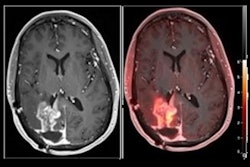

(A) A 76-year-old male patient with left precentral IDH wild-type glioblastoma before hypofractionated radiotherapy and temozolomide chemotherapy. Tumoral TSPO radioligand uptake was high (SUVmax, 2.4), and survival was short (OS, 4.5 months). (B) A 71-year-old female patient with left postcentral parietal IDH wild-type glioblastoma before hypofractionated radiotherapy and temozolomide chemotherapy. Tumoral TSPO radioligand uptake was low (SUVmax, 1.8), and survival was long (OS, 25.8 months). Image and caption courtesy of the Journal of Nuclear Medicine (CC BY 4.0).The patients' median progression-free survival was 8.1 months and overall survival was 10.8 months. At the last treatment follow-up, 43 of 45 patients (95.6%) had experienced tumor progression and 40 of 45 patients (88.9%) had died.

According to the findings, tumoral uptake of F-18 GE-180 on the PET imaging was associated with overall survival. Specifically, a high maximum standard uptake value (SUVmax) was related to significantly shorter overall survival: 8.3 months versus 17.8 months, the researchers found.

"Compared with patients with low tumoral uptake on TSPO-PET, patients with SUVmax of more than 2.2 had a significantly higher risk for death, with a hazard ratio of 2.2 in the multivariate analysis," the group wrote.